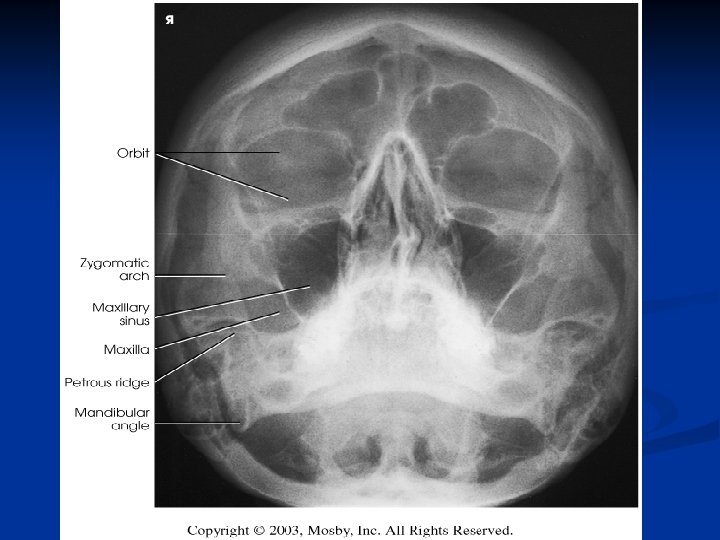

Waters Radiograph n Distance from lateral border of skull and orbit equal on each side n Petrous ridges projected immediately below maxillary sinuses

Reverse Waters Radiograph n Distance from lateral border of skull and orbit equal on each side n Petrous ridges projected immediately below maxillary sinuses

Modified Waters Radiograph n Petrous ridges projected immediately below the inferior border of the orbits n Equal distance from lateral orbit to lateral skull on both sides